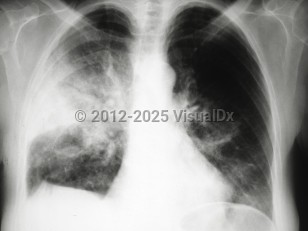

Pleural effusionPleural effusion

Pulmonary edema

Acute eosinophilic pneumoniaAcute eosinophilic pneumonia

Acute interstitial pneumoniaAcute interstitial pneumonia

Chronic eosinophilic pneumonia

Cryptogenic organizing pneumoniaCryptogenic organizing pneumonia

Nonspecific interstitial pneumonia

Pulmonary fibrosis

Desquamative interstitial pneumonia

Acute respiratory distress syndromeAcute respiratory distress syndrome

Drug-induced pneumonitis